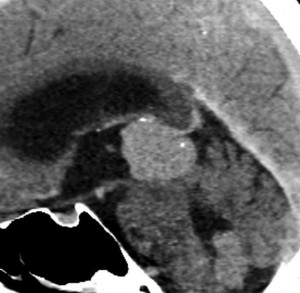

第3脳室開窓後のCTです。左のCTでは小さな石灰化がみられます。右の造影CTでは小さなのう胞部分をのぞいて均一な増強効果がみられます。